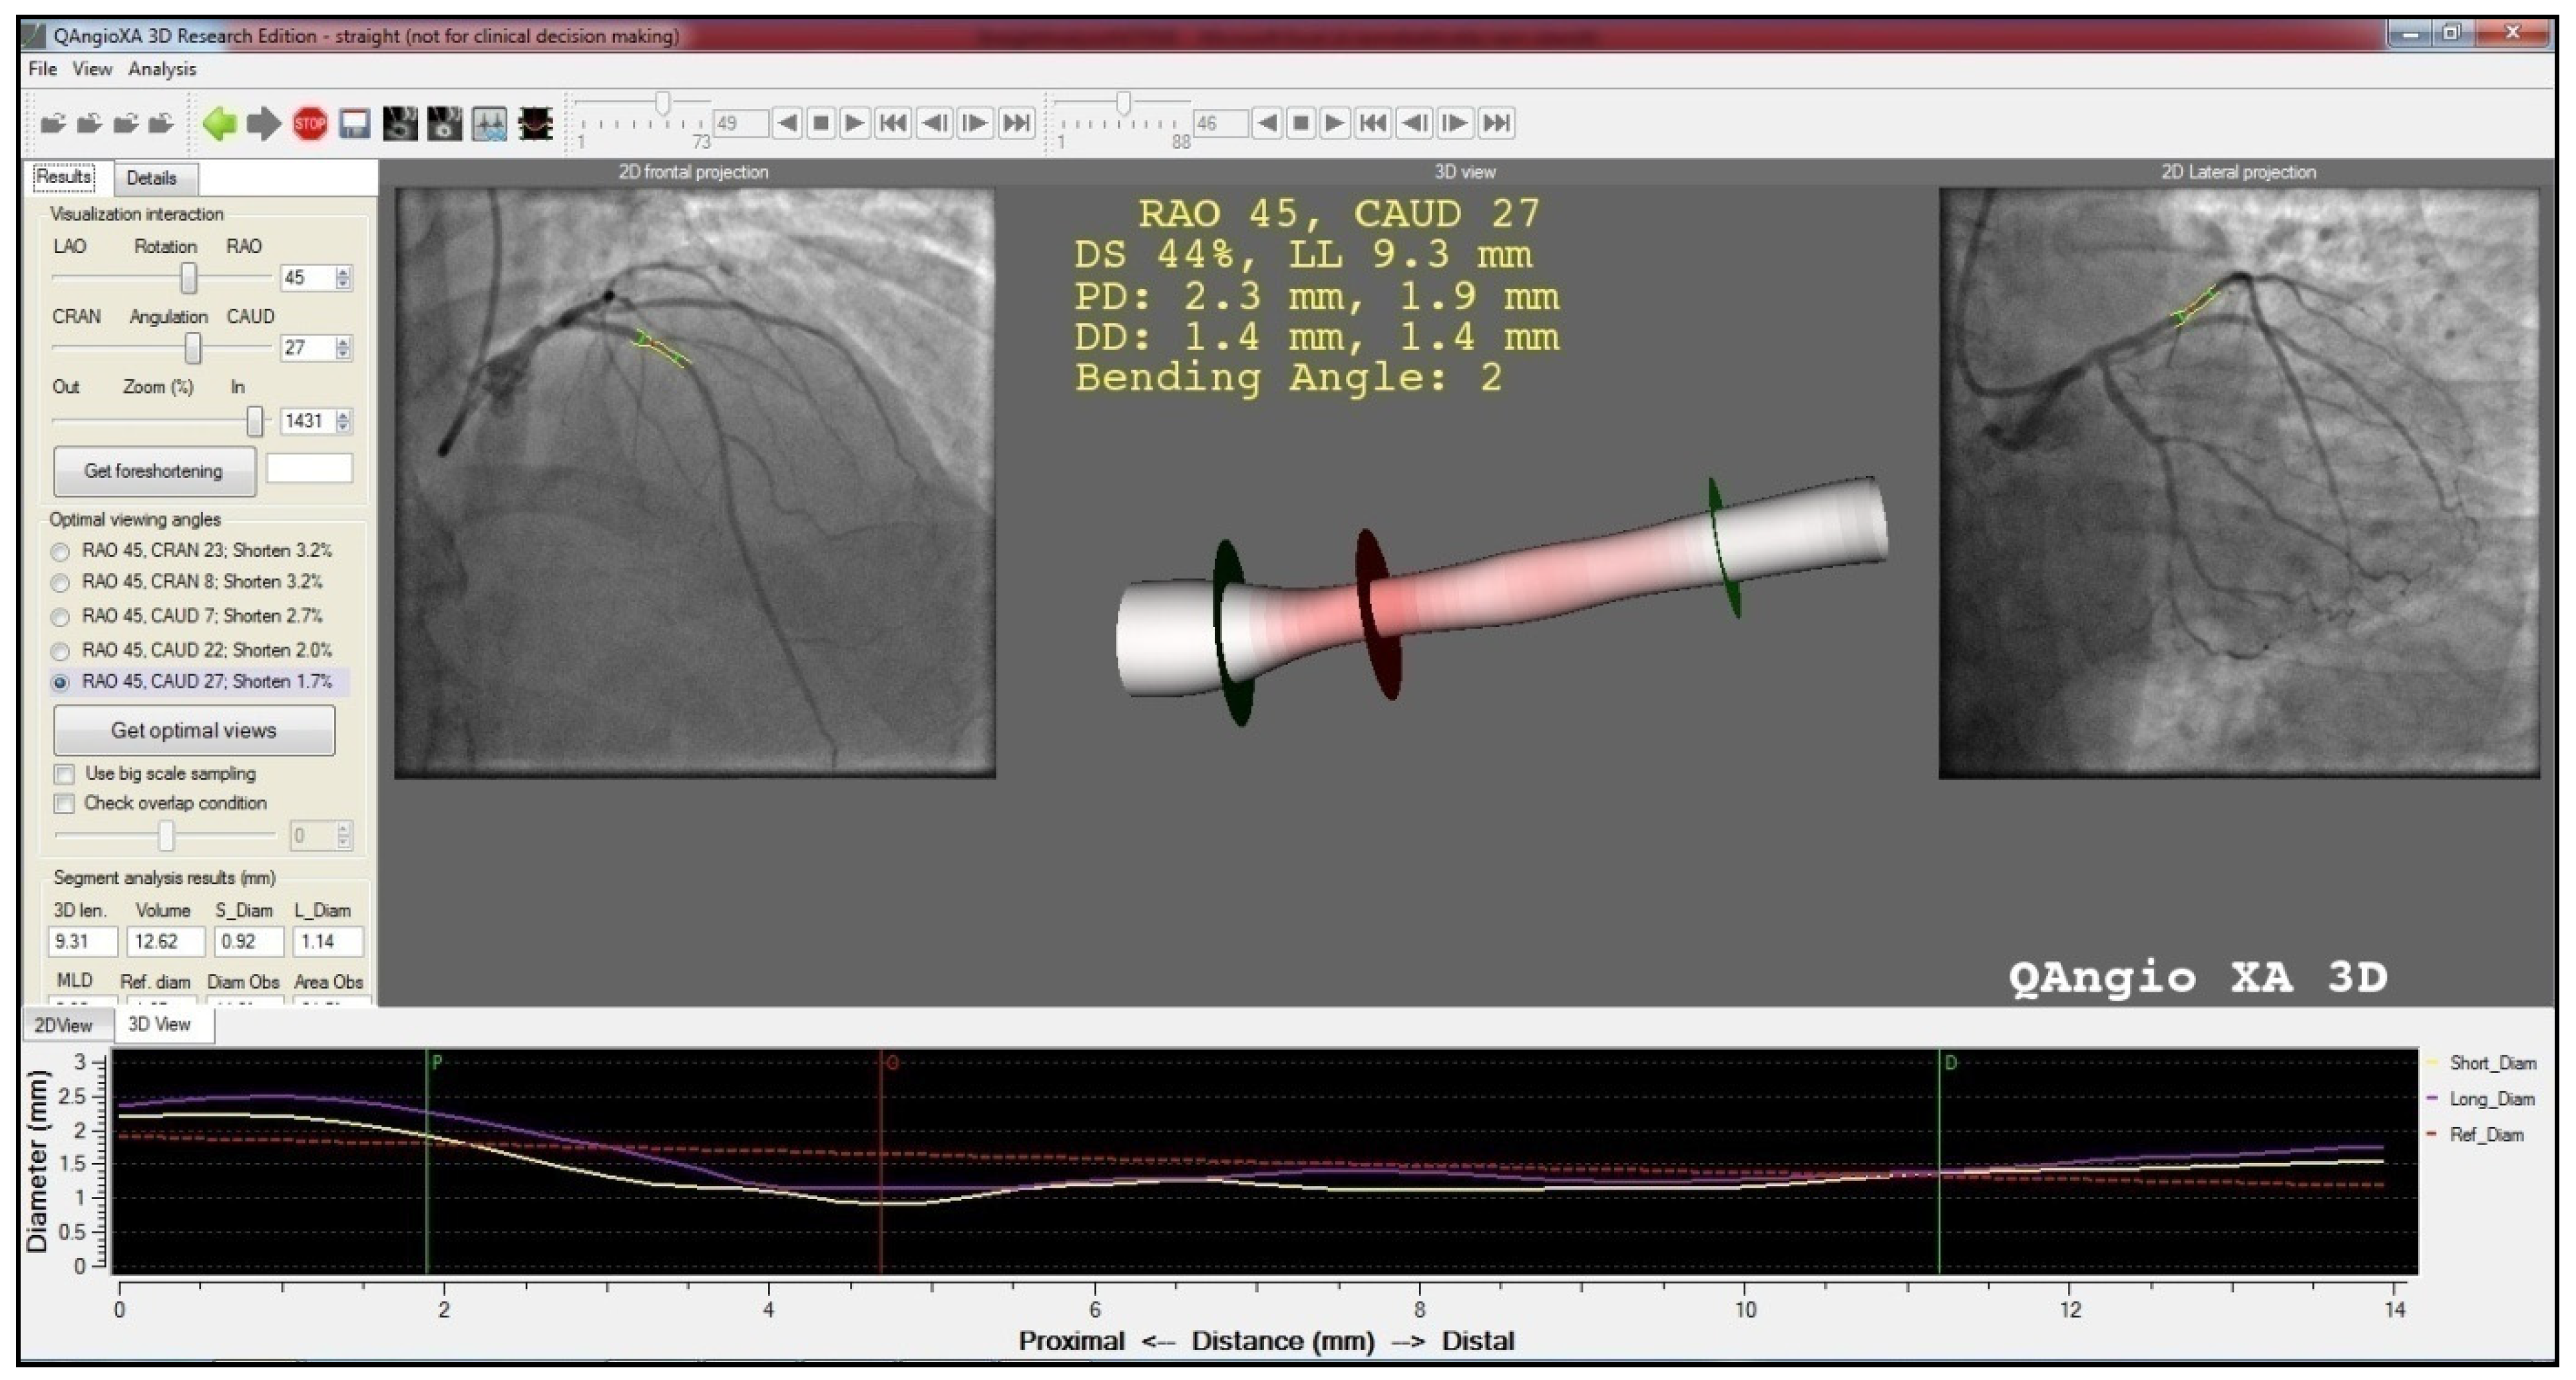

2. Methods

4. Results

| 3D obstruction length (mm) | 18.90 ± 13.64 | 20.54 ± 18.79 | 0.551 |

| Minimal lumen diameter (mm) | 0.92 ± 0.32 | 0.95 ± 0.29 | 0.561 |

| Reference diameter at MLD (mm) | 2.17 ± 0.47 | 2.20 ± 0.52 | 0.726 |

| Percent diameter obstruction at MLD (%) | 56,99 ± 13.05 | 55.87 ± 12.65 | 0.602 |

| Percent area obstruction at MLD (%) | 68.83 ± 14.38 | 64.47 ± 12.65 | 0.106 |

| Minimal lumen area (mm2) | 1.05 ± 0.55 | 1.20 ± 062 | 0.126 |

| Reference area at MLA (mm2) | 3.81 ± 1.72 | 4.02 ± 1.20 | 0.484 |

| Area obstruction at MLA (%) | 70.52 ± 13.3 | 67.50 ± 14.94 | 0.201 |

| Obstruction segment mean diameter (mm) | 1.79 ± 0.35 | 1.89 ± 0.42 | 0.127 |

| Obstruction segment volume (mm3) | 58.29 ± 61.27 | 77.38 ± 117.05 | 0.224 |

| Obstruction segment plaque volume (mm3) | 23.90 ± 27.08 | 24.78 ± 33.84 | 0.863 |

| Obstruction segment reference volume (mm3) | 79.32 ± 81.93 | 97.72 ± 141.50 | 0.343 |

| Obstruction segment mean reference diameter (mm) | 2.17 ± 0.45 | 2.21 ± 0.52 | 0.624 |

| Arch-chord ratio | 1.07 ± 0.09 | 1.10 ± 0.19 | 0.180 |

| Lesion eccentricity index | 0.27 ± 0.15 | 0.23 ± 0.12 | 0.106 |